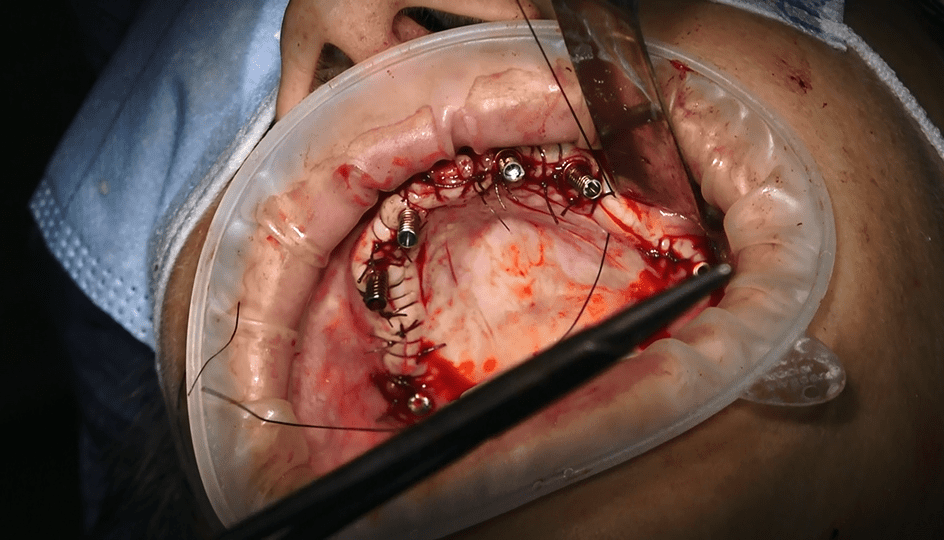

• Il video documenta ogni fase dell’intervento, dalla progettazione personalizzata della griglia sottoperiostea all’applicazione dei singoli impianti e, infine, alla realizzazione di una protesi dentale a carico immediato.

• Durante l’intervento chirurgico, la griglia sottoperiostea viene posizionata direttamente sull’osso mascellare, fornendo un supporto stabile per gli impianti dentali.

• Una delle caratteristiche distintive di questa tecnica è il carico immediato. Subito dopo l’inserimento della griglia e degli impianti, viene applicata una protesi dentale fissa provvisoria, consentendoti di avere denti fissi fin dalla stessa giornata dell’intervento.